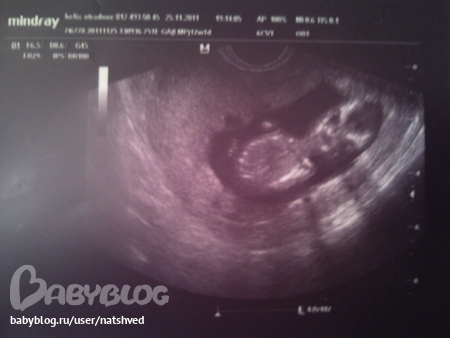

Сегодня же ходила на первый скрининг, так мило!!!! Мой малыш в полном порядке, все соответствует норме, КТР 62мм, БПР 17,3мм, ДБ 7,5мм, ТВП 1,2мм, ЧСС 159 уд./мин.. Нос, ручки, ножки, желудок, сердечко, позвоночник, пальчики и половой отросточек - все есть! Активно шевелемся, переворачиваемся. В начале узи он был спиной кверху, потом перевернулся спиной вниз, потом на бок спиной, потом животом, а в конце вообще вниз голвой))) Сначала все челюстями чмокал, вроде как ел или пил)))Рассмешил меня, когда врач показала, что он двсе время держит одну руку между ног))))начесывает там себе что то, так делают в основном мальчики, мне кажется))))но она по углу отростка предположила, что это скорее всего девочка! Я так и знала! Не зря сны снились. Хотя, думаю, что рано еще для точного определения пола. Так что будем ждать 20 недель. Мужу и сыну сказала, что предположительно девочка, расстроились. А я сказала: ну и хорошо! помощница будет!

А вот и фоточки: на верхнем, как будто улыбается))), на средней инопланетянин, а на нижней рукой махает)))